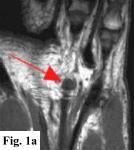

MRI FINDINGS:   MRI was performed on AIC's high-field 1.5 Tesla short-bore Siemens Symphony scanner using a small flexible surface coil. Fig. 1a is a high-resolution coronal DESS, Fig. 1b a sagittal T1 weighted, Fig. 1c a sagittal turbo STIR, and Fig. 1d an axial T1 weighted. They demonstrate a 5x5x7 mm nodule in the volar aspect of the hand at the level of the 4th MCP joint inseparable from the flexor digitorum superficialis tendon (arrows) with some adjacent soft tissue edema. The underlying tendon and bones are otherwise intact.

SURGICAL-PATHOLOGIC DIAGNOSIS:   The patient was taken to surgery at LCH by Dr. Rahmati and a "rather solid round mass attached to the volar aspect of the 4th tendon sheath" (arrows in Fig. 2a-b) was excised measuring about 4x4x3 mm. Pathology at LCH revealed a "grayish-white somewhat nodular smooth soft tissue measuring 9x8x5 mm" with histopathologic "features in favor of a giant cell tumor of tendon sheath" interpreted as benign.